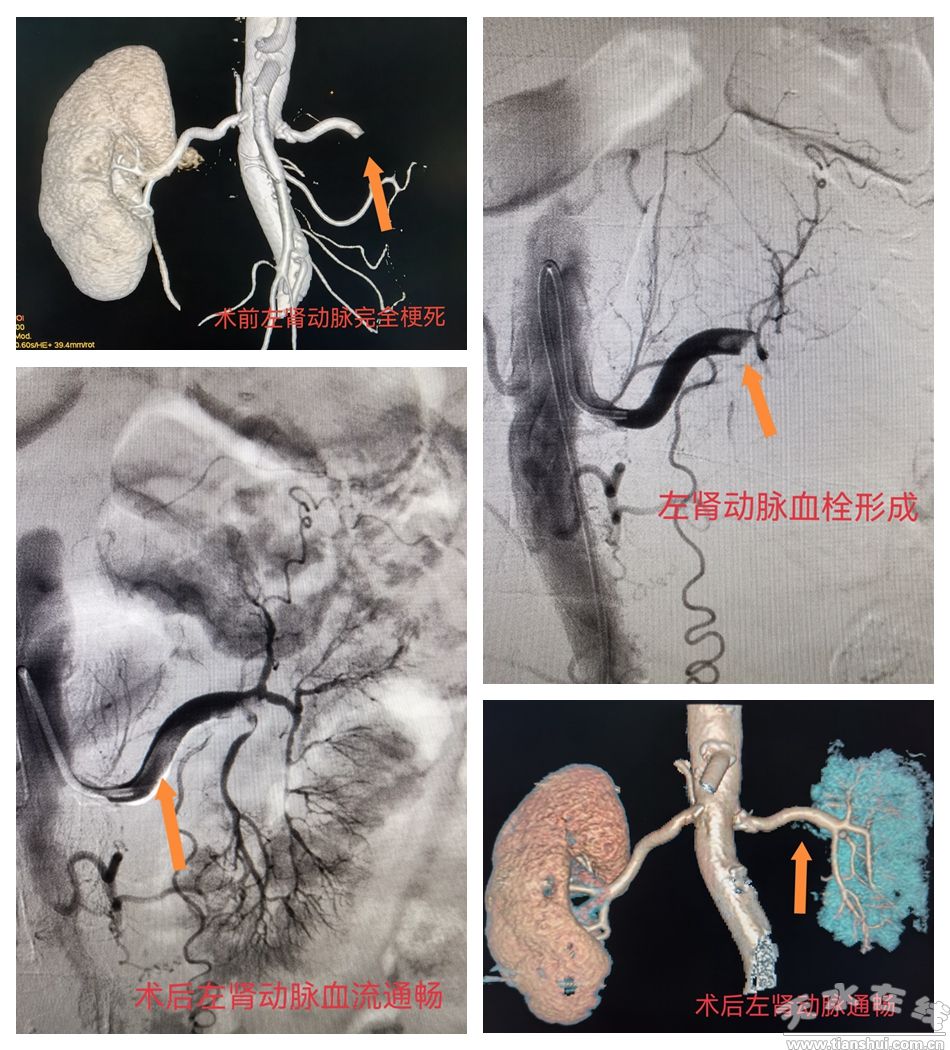

近日,天水市第四人民醫(yī)院介入醫(yī)學(xué)科成功為一名急性腎動(dòng)脈栓塞患者實(shí)施血栓清除手術(shù),精準(zhǔn)開通閉塞血管,阻斷腎臟缺血壞死進(jìn)程,守護(hù)了患者腎功能。

患者為老年女性,因“突發(fā)左側(cè)腰腹部劇痛1天余”緊急前往我院急診科就診。接診醫(yī)生高度警惕,立即啟動(dòng)“綠色通道”為患者安排腹部增強(qiáng)CT檢查,提示左腎動(dòng)脈完全閉塞、腔內(nèi)大量血栓,且肌酸激酶、D-二聚體及腎功能指標(biāo)均明顯異常,已出現(xiàn)腎臟缺血壞死征象。急性腎動(dòng)脈栓塞發(fā)病急、進(jìn)展快,延誤治療易導(dǎo)致腎功能衰竭,患者情況十分危急。

急診科第一時(shí)間啟動(dòng)緊急預(yù)案,組織多學(xué)科(MDT)專家會(huì)診,最終確定采用介入微創(chuàng)治療方案——腎動(dòng)脈取栓術(shù)+置管溶栓術(shù),以快速恢復(fù)腎臟血供。手術(shù)全程歷時(shí)1.5小時(shí),在局部麻醉下順利完成。醫(yī)生通過微創(chuàng)穿刺建立通路,將導(dǎo)管精準(zhǔn)送達(dá)閉塞部位,成功清除血栓并留置溶栓導(dǎo)管持續(xù)治療。整個(gè)手術(shù)過程安全高效、創(chuàng)傷小,有效避免了傳統(tǒng)開放手術(shù)的大創(chuàng)傷及腎切除風(fēng)險(xiǎn)。

術(shù)后,患者被轉(zhuǎn)入介入醫(yī)學(xué)科住院觀察治療。術(shù)后第3天復(fù)查顯示,腎動(dòng)脈血流通暢,腎功能逐步改善,腰腹部劇痛癥狀快速緩解;住院第7天,患者各項(xiàng)指標(biāo)趨于穩(wěn)定,達(dá)到出院標(biāo)準(zhǔn)順利出院,恢復(fù)情況良好。